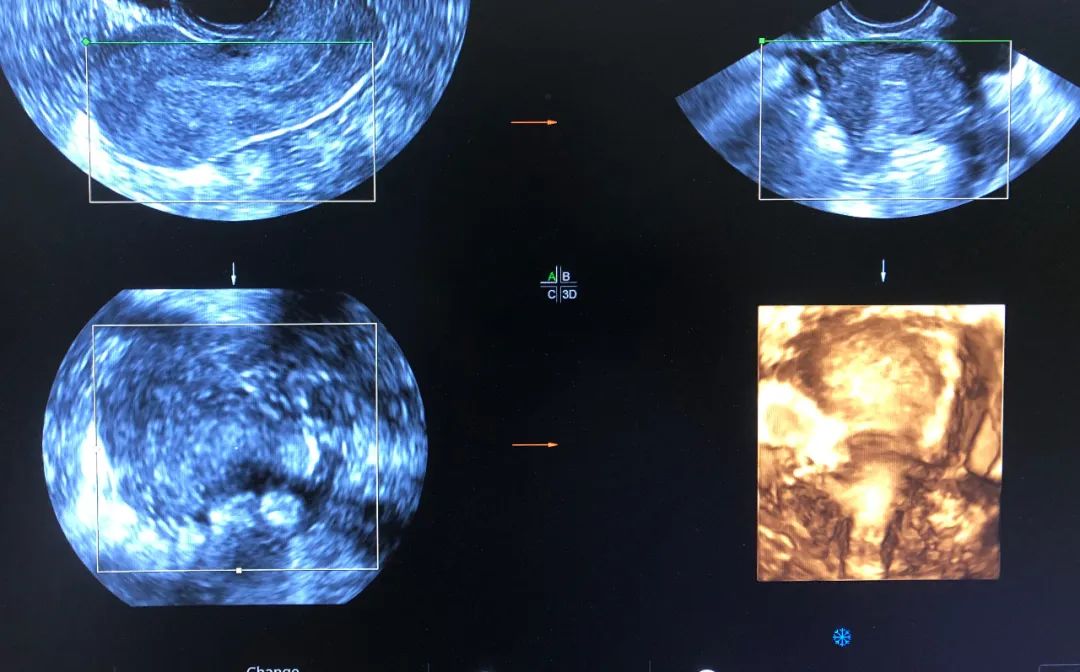

6月2日,一患者因外院超声诊断不全纵隔子宫来市妇幼院就诊,经常规妇科超声检查并未发现明显纵隔,与患者沟通后行经阴道四维超声检查,得到了清晰的图像诊断为弓形子宫,为妇科临床诊断提供了可靠依据。

腔内四维超声(4D-TVS)是在腔内二维超声基础上,利用计算机处理发展起来的新型超声诊断技术,可以提供更多的诊断信息,具有常规经阴道超声无法比拟的优势,立体直观,功能强大,可实现360度全方位无死角成像,大大弥补了单纯二维腔内超声的不足。

腔内四维超声检查可对先天性子宫畸形(完全或不完全纵隔子宫、弓状子宫、双角子宫、单角子宫、残角子宫等)、宫腔粘连、内膜息肉、粘膜下肌瘤进行诊断及鉴别诊断,还能清晰的观察到节育器的形态、位置,大大提高了超声在妇科疾病诊断中的准确率,为临床医生提供更准确的诊断信息,同时填补了我市在此项技术的空白。